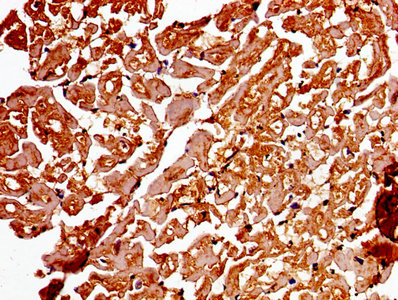

Immunohistochemistry of paraffin-embedded human heart tissue using CSB-PA001311LA01HU at dilution of 1:100

IHC image of CSB-PA001311LA01HU diluted at 1:250 and staining in paraffin-embedded human lung tissue performed on a Leica BondTM system. After dewaxing and hydration, antigen retrieval was mediated by high pressure in a citrate buffer (pH 6.0). Section was blocked with 10% normal goat serum 30min at RT. Then primary antibody (1% BSA) was incubated at 4°C overnight. The primary is detected by a biotinylated secondary antibody and visualized using an HRP conjugated SP system.